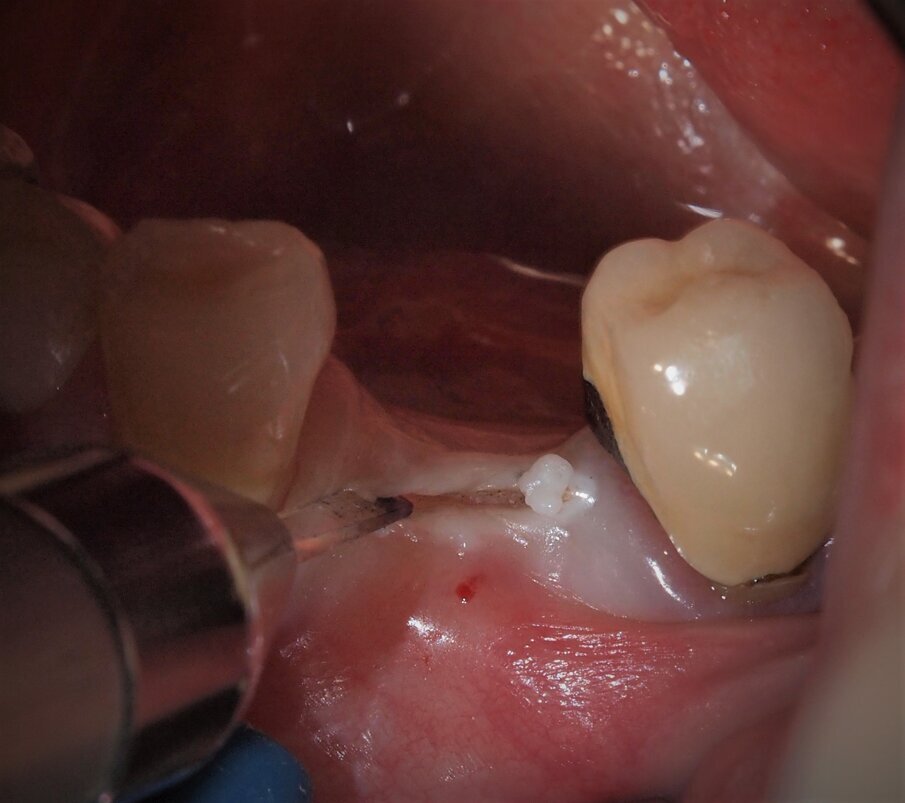

Fig. 3 - Caso clinico 1. Incisione dei tessuti molli con laser a diodi da 915 nm ed inserto in zaffiro. Si osservi l’annerimento della porzione terminale dell’inserto, ad indicarne l’avvenuta attivazione.

Fig. 4 - Caso clinico 1. Incisione dei tessuti molli con laser a diodi da 915 nm e inserto in zaffiro. L’inserto viene condotto lentamente con un movimento simile a quello della lama fredda.

Fig. 5 - Caso clinico 1. Incisione dei tessuti molli con laser a diodi da 915 nm e inserto in zaffiro. Si apprezza macroscopicamente l’assenza di fenomeni di carbonizzazione.